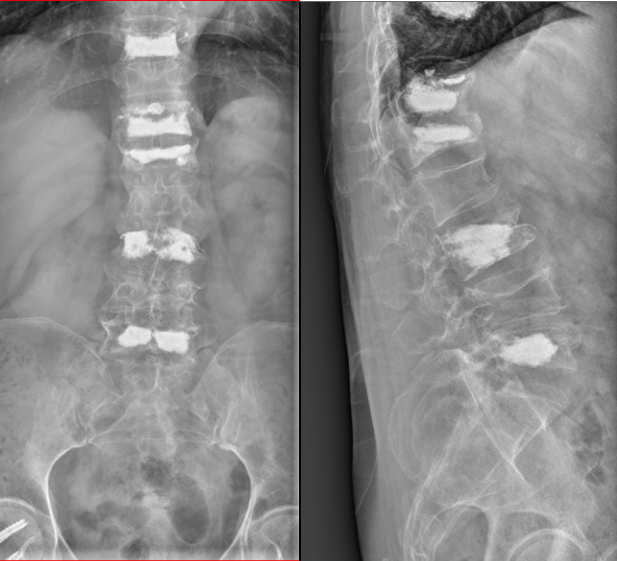

虽然术后的X光片看起来令人触目惊心,但实际上,这些复杂的手术都是通过微小的切口完成的。最大的伤口只有1公分大小,最多只需缝合一针。而背部的切口更是小得如同“小眼”一般,无需缝合和拆线。大约一周后,谢某就可以自行移除纱布了。

检查结果显示,谢某的身体状况良好,但骨折情况却相当严重。除了右侧股骨颈骨折伴有错位外,还有胸10、胸12、腰1、腰3和腰5等5个椎体的新鲜骨折。面对如此严重的多发骨折,传统的手术方式显然不是最佳选择,因为就算是年轻人也难以承受长时间的手术和麻醉。针对这一特殊情况,张镇提出了分多次进行微创手术的方案。这样既可以减少手术对患者身体的负担,又能达到最佳手术治疗效果。

按照术前计划,谢某首先接受了腰麻下的股骨颈骨折闭合复位空心钉内固定术。手术过程非常顺利,四十分钟便完成了。术后观察期间,医生为她进行了精心的后续治疗。病情稳定后,又为谢某做了两次腰椎骨折的微创手术。每次手术过程都是同样短暂,但效果极佳。局部麻醉的运用,谢某在手术过程中几乎感觉不到任何痛苦。